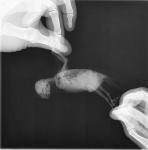

Ромашка :) Опубликовано 23 апреля, 2016 Автор #33 Опубликовано 23 апреля, 2016 Курита, Здесь на форуме прочла, что волнистых попугаев как вид полностью уже испортили, загубили. Очень много умирают от опухолей врач мне то же самое сказал.. Delfin, ольга 84, Курита, - Спасибо вам за поддержку! Delfin -дай бог выжить... врач сказал - не выживет... Посмотрите, какой Ромочка на рентгене

Ромашка :) Опубликовано 24 апреля, 2016 Автор #34 Опубликовано 24 апреля, 2016 (изменено) Были у врача Томашевского Александра в Белый Клык. Осмотрев птицу Александр сразу сказал- опухоль семенника, предложил не делать рентген, т.к. дорого и нет смысла, но я бы потом всё время думала, а вдруг..? и поэтому решила рентген сделать. Рентген подтвердил диагноз. Назначили антибиотик и обезболивающее. Сколько Роме осталось я не спрашивала, не могу... Александр сказал- если будет совсем плохо, усыпить.. Я умом всё понимаю, сердцем нет В нашем случае действительно НУЖНО БЫЛО СРАЗУ ПОЙТИ К ВРАЧУ!! По крайней мере я бы не потратила 2000 на анализы, нам анализы оказались не нужны..... Пушистик просит есть, но кашу не ест и всё! Опять кормила через зонд- если орёт с зондом во рту, это я правильно попала? В первый раз обратно пошла каша с непереваренными зёрнами , много дала? ( страшно, а что делать..)Неперевареные зёрна в 12 ночи??? Поел в 3 дня и почему не переваривается?? Теперь только мягкий корм, у Ромы опустился желудок вниз и сдавлен опухолью, поэтому мало какает. Скажите, от мягкого корма понос это нормально? ОЧЕНЬ помогла эта ссылка *Кормление Через Зонд КОРМЛЕНИЕ ЧЕРЕЗ ЗОНДи тема DelfinКстати, спрашивала зонд 18 сказали нет, потом нашли такой, девушка не могла на нём № найти, мелко в уголке написано 21G Кормлю кашей Помогайка от Нестле, написано там пробиотики и пребиотики, дополнительно нужно что-нибудь? А попугай чувствует сытость при кормлении через зонд?? Изменено 24 апреля, 2016 пользователем Ромашка :)

Delfin Опубликовано 24 апреля, 2016 #35 Опубликовано 24 апреля, 2016 увы, ренгены читать не умею, могу только явные траблы с костями еще глянуть.... ГКС назначили для уменшения опухоли? - если выписали только обезбал и антиб - стучитесь к Зосе и просите лечение от опухоли. Да, шансы мизерные, НО: можно продлить птице жизнь без боли.Если орет с зондом - то правильно, зонд в пищеводе. Если пошла рвота едой при зондировании -это значит птиц поел перед этим -и понятно что рвотный рефлекс получился -птицу вырвало. ЛИБО зоб был полный, и вы еще зондом накормили -поэтому всегда проверять зоб на ощупь!!От мягкой еды, каш конечно же будет светлый и жидкий помет. Я уже привыкла про номера катетером - както тут сравнили по диаметру катетеры разных номеров - оказалось ТРУБКА везде одна и та же, отличаются лиш диаметром самой ИГЛЫ.Про кашу - лучше взять кашу для ручного вскармливания птенцов попугаев Нутриберд - там уже все есть что нужно. Если берете детские безмолочки или сами делаете -то я добавляю пробиотик, карсил (у нас с вами печень увеличина), ферменты поджелудочной, нистатин (если даете антибиотик, да и вообще - прикормлении зондом есть риск получить кандидоз)Про сытость через зонд - не могу сказать... порой он сразу идет спать, а порой после зонда бежит еще немного зерна поклюет (я никогда зоб до отказа не набиваю, даю по 1,5-2 мл)